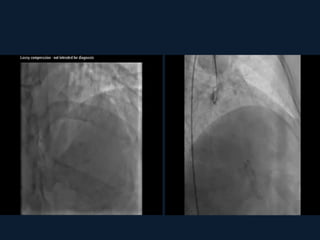

1.CORONARY CTA

2.CONVENTIONAL ANGIOGRAPHY

• DIAGNOSIS: 1.CORONARY CTA 2.CONVENTIONALANGIOGRAPHY 3.IVUS(INTRAVASCULAR US) AND ICD(INTRA- CORONARY DOPPLER ) 4. MRI